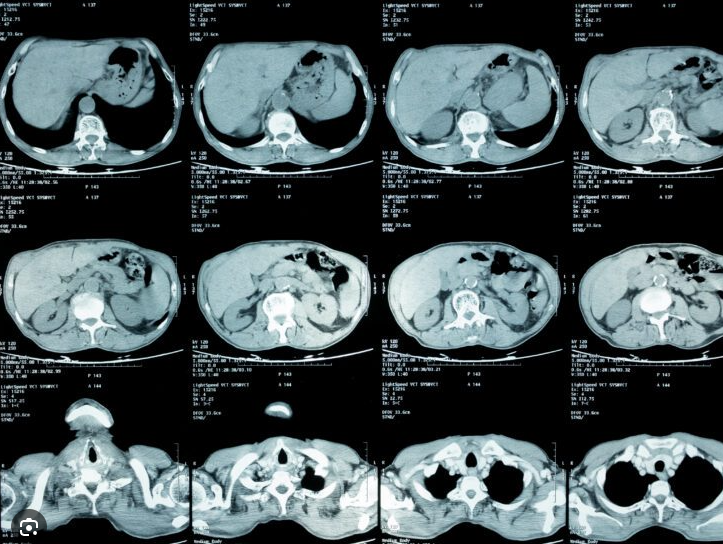

Computed tomography has become the single most important imaging modality in the evaluation of FUO, with sensitivities ranging from 60-92% depending on the specific site of involvement and the pathology being sought. CT of the abdomen and pelvis is particularly valuable for identifying occult abdominal pathology including occult abscess, necrotic lymph nodes suggesting tuberculosis or lymphoma, splenic infarction, or other sources of fever. CT of the chest is valuable for identifying pneumonia, mediastinal pathology, and other thoracic sources of fever.

CT imaging is the single most important imaging modality in FUO evaluation. CT abdomen/pelvis, chest, and pulmonary angiography are commonly used; MRI excels for CNS, vascular, and soft tissue pathology.